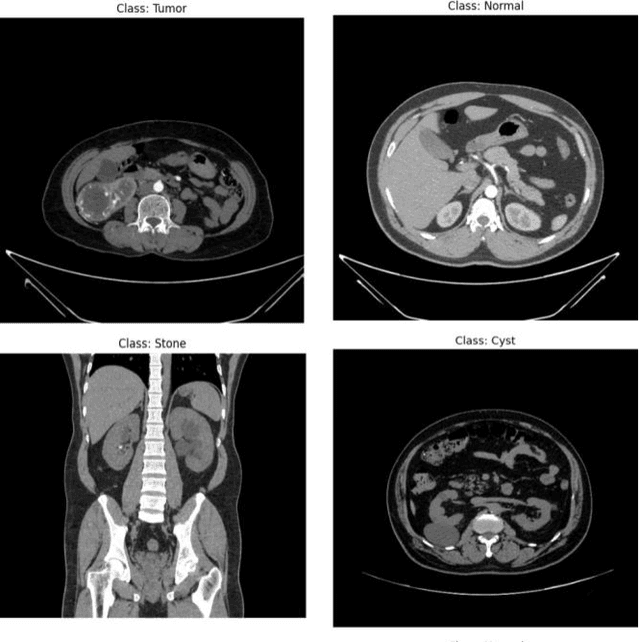

Abstract:Chronic Kidney Disease (CKD) represents a significant global health challenge, characterized by the progressive decline in renal function, leading to the accumulation of waste products and disruptions in fluid balance within the body. Given its pervasive impact on public health, there is a pressing need for effective diagnostic tools to enable timely intervention. Our study delves into the application of cutting-edge transfer learning models for the early detection of CKD. Leveraging a comprehensive and publicly available dataset, we meticulously evaluate the performance of several state-of-the-art models, including EfficientNetV2, InceptionNetV2, MobileNetV2, and the Vision Transformer (ViT) technique. Remarkably, our analysis demonstrates superior accuracy rates, surpassing the 90% threshold with MobileNetV2 and achieving 91.5% accuracy with ViT. Moreover, to enhance predictive capabilities further, we integrate these individual methodologies through ensemble modeling, resulting in our ensemble model exhibiting a remarkable 96% accuracy in the early detection of CKD. This significant advancement holds immense promise for improving clinical outcomes and underscores the critical role of machine learning in addressing complex medical challenges.